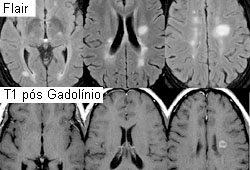

Ressonância nuclear magnética (RNM) com recuperação da inversão atenuada de fluido (FLAIR) e agente de contraste gadolínio, exibindo lesões típicas observadas na esclerose múltipla (EM) nas regiões periventriculares.

Do acervo pessoa de Lael A. Stone, Mellen Center for MS Treatment and Research, Neurological Institute, Cleveland Clinic Foundation; usada com permissão